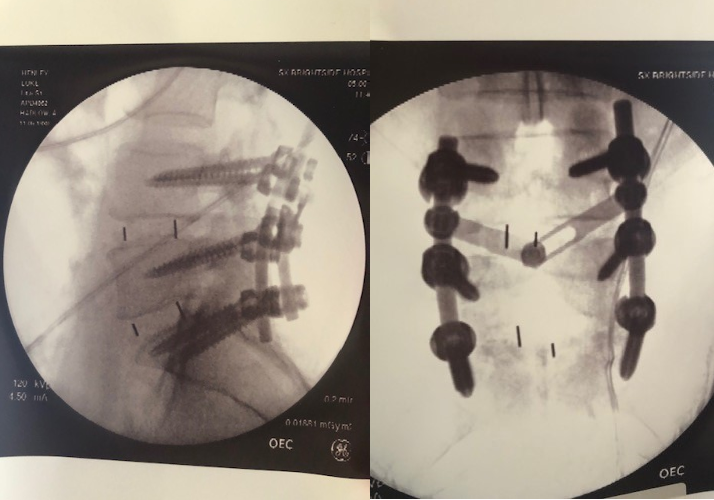

Visuals of Luke's spine post-surgery